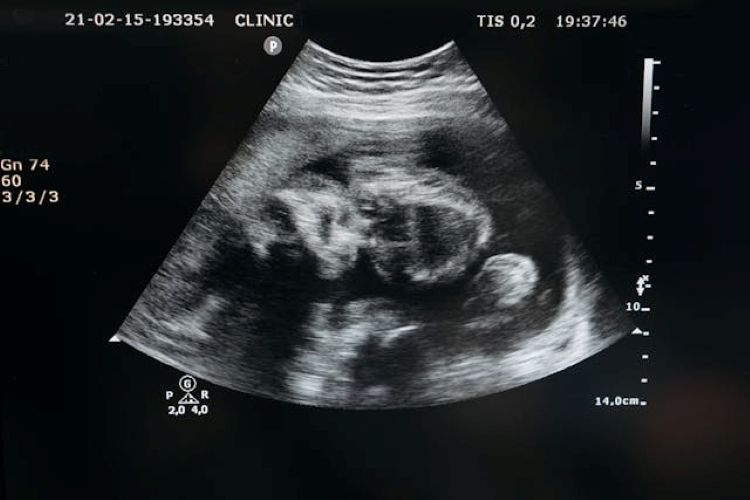

Artificial wombs, devices that can gestate human embryos outside the body, have shifted from speculative fiction to the brink of medical reality. Recently, a Chinese firm made headlines by announcing plans for a humanoid robot with a built-in artificial womb, promising a prototype by 2026. The technology was estimated to cost USD $14,000.

The science of AWT is real, although limited. Current experiments represent partial ectogenesis: where a foetus begins developing in the uterus and is then transferred to an artificial womb to continue its growth. Scientists in the US, the Netherlands and Japan have sustained premature animal foetuses in external ‘biobags‘.

Full ectogenesis (a baby never incubated in a human womb) may still be decades away, dependent on breakthroughs in placental bioengineering, infection control, and safely initiating embryo growth outside the uterus. But history suggests we should not underestimate incremental breakthroughs. In-Vitro Fertilisation (IVF) too, was once dismissed as fantasy until Louise Brown, the first ‘test-tube baby’, was born in 1978.